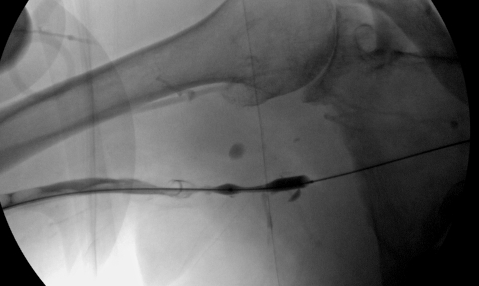

Balloon dilation of RBV stenosis

Balloon dilation of critical venous stenosis distal to the AV graft.